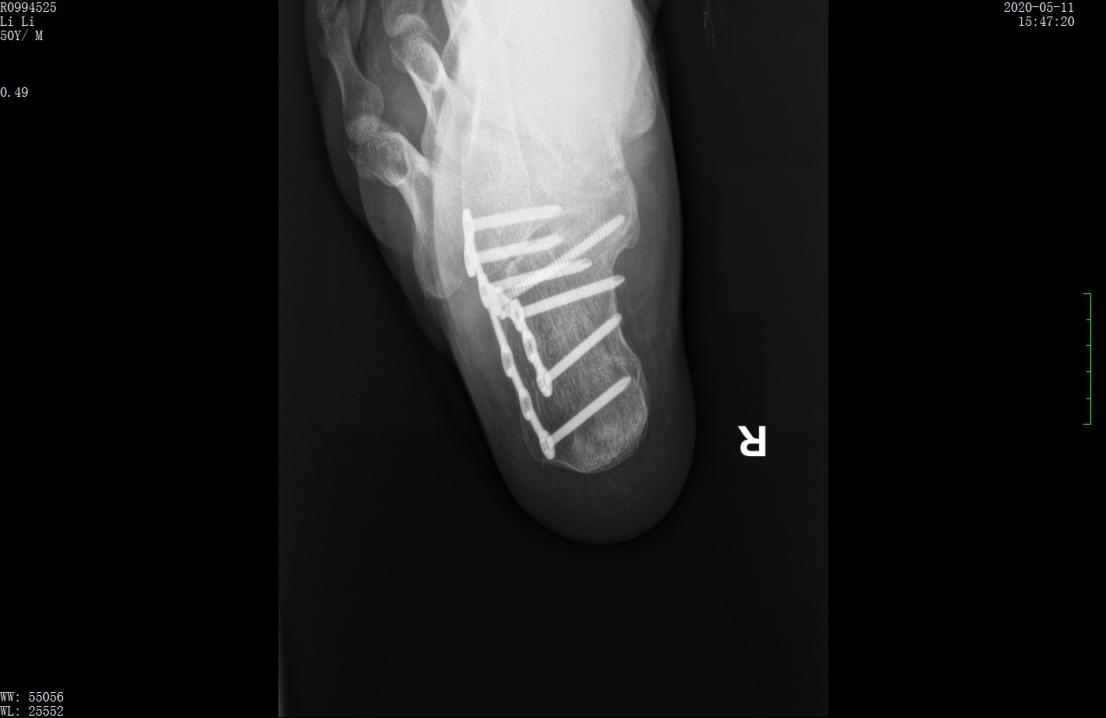

行微创手术治疗后,跟骨高度恢复,关节面平整

4cm长的手术切口,避免了切口并发症